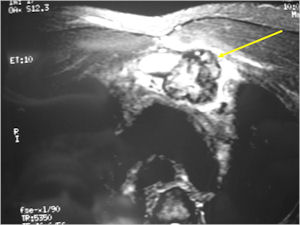

MRI:

- Also useful in determining extent

- There is often extensive edema around the tumor in the surrounding bone and soft tissues that can lead to a misdiagnosis of a malignant tumor.

- Aggressive osteoblastomas are usually larger than a conventional osteoblastoma and have been reported to be up to 8.5 cm in diameter.

- Most have a similar radiographic appearance as a conventional osteoblastoma and have well defined margins, variable amounts of mineralization and peritumoral sclerosis. They occasionally have radiographic characteristics consistent with malignancy.